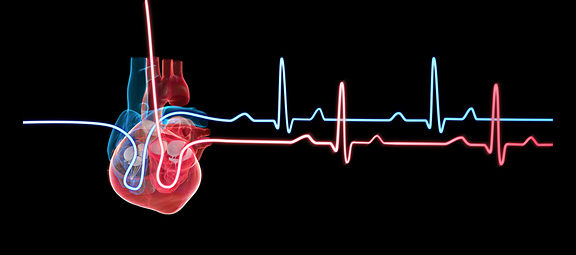

הלב כולו הוא שריר, וכמו כל השרירים הוא מקבל את הוראות ההפעלה שלו מהמוח. אילוסטרציה של הלב ופעימות הלב | Tumeggy / Science Photo Library